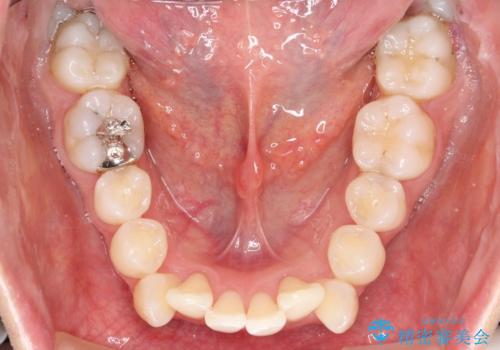

- 出っぱによる口元の閉じにくさを主訴に来院されました。上顎の出っ歯と上下顎叢生も認められたため、上下顎両側4番抜歯を行い、ワイヤー矯正で治療する治療計画を立てました。

上顎にはMI(マイクロインプラント)を埋入して固定源とすることで出っ歯の改善を図りました。

少しスペースクローズに時間がかかりましたが、MIを用いたワイヤー矯正で

主訴である出っ歯と叢生が改善されました。口も閉じやすくなり、スッキリとした口元になりました。